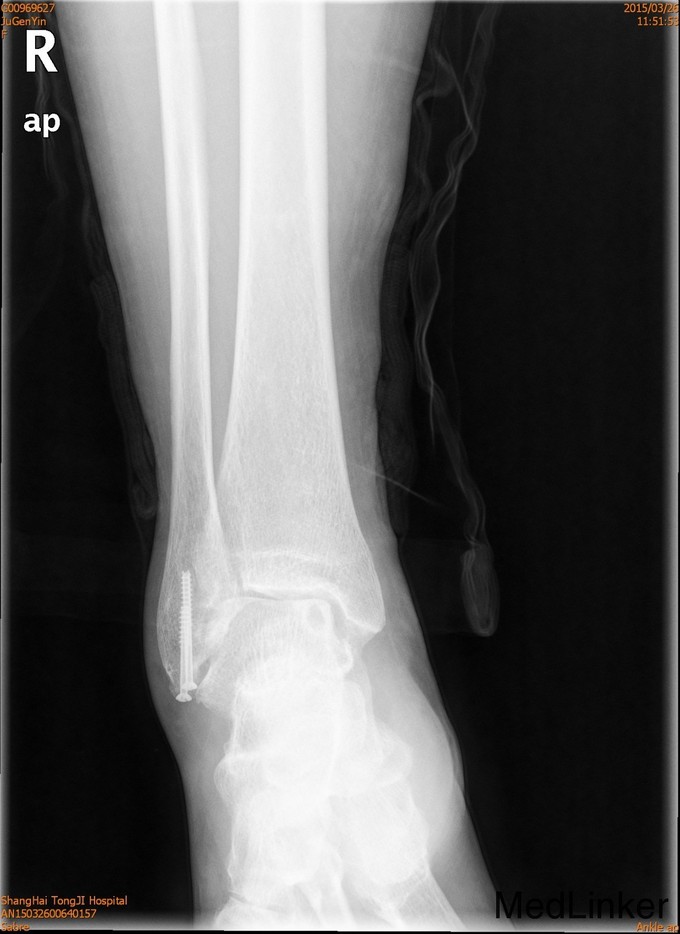

患者女,61岁,摔伤后右踝足肿痛4天。患者4天前不慎摔伤,即感右足踝疼痛,肿胀,活动受限 ,休息后疼痛减轻,X线示右外踝骨折。

查体:一般情况可,右外踝肿胀,淤青,压痛明显,可及骨擦感,足部活动感觉可。

诊断为右外踝骨折,完善术前检查后于全麻下行右外踝骨折ORIF术+距腓前韧带修复术。

2年后随访患者活动可,内固定位置可,螺钉未予取出。外踝骨折可导致踝关节不稳定,手术治疗效果可。